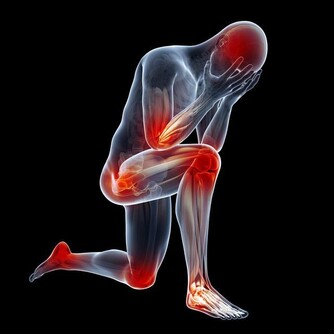

反復性的呼吸暫停,會造成人體內血氧飽和度下降和二氧化碳瀦留,使患者睡眠質量降低,即使睡了七八個小時,白天依舊易困倦、疲勞。最典型的後果即是車禍,在美國,患者發生車禍的概率是常人的2-3倍。

2. 猝死

呼吸道通氣功能障礙會導致心臟供氧不足,心臟處於收縮期,可能引發猝死。